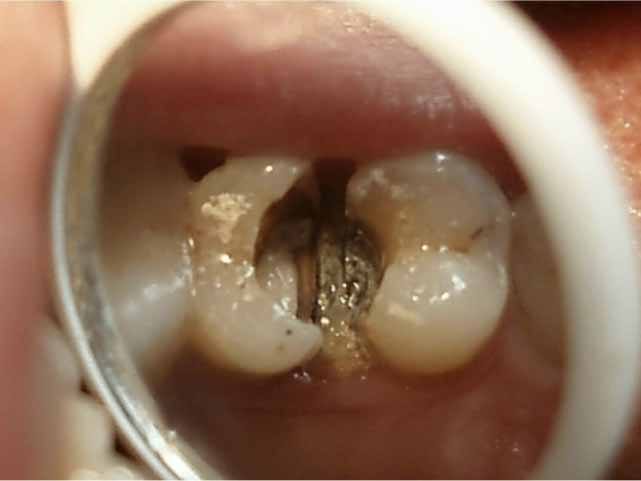

5、龋洞

检查时可能见到较深的龋洞,探诊时牙齿疼痛明显。或会发现畸形中央尖、畸形舌侧窝等可能导致牙髓炎的情况。